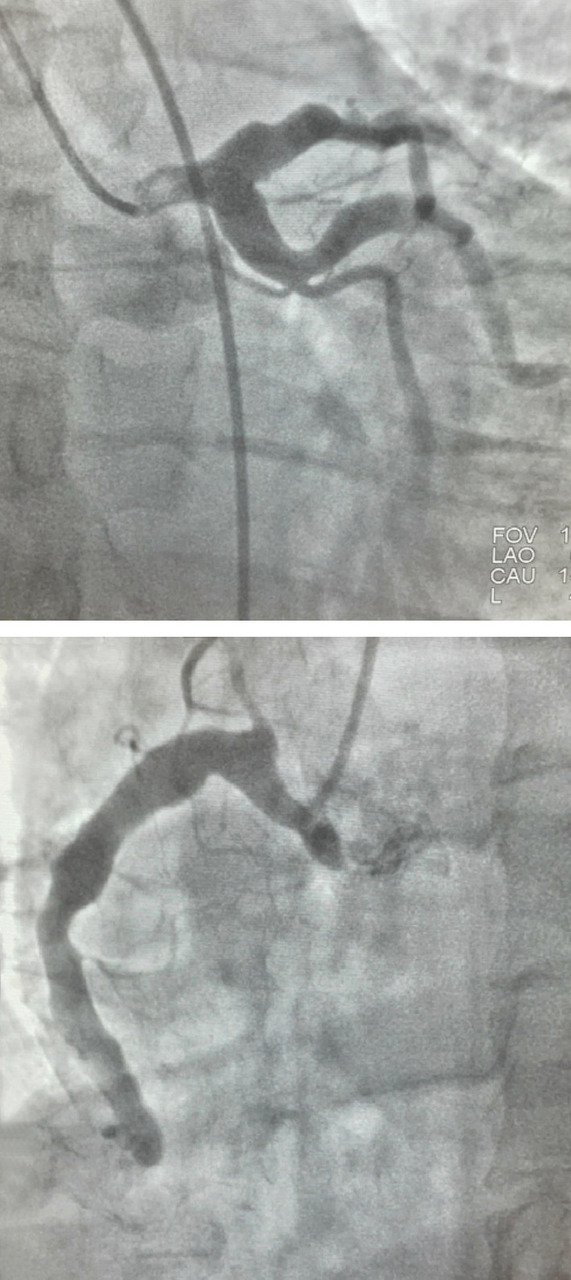

Une coronarographie est réalisée et révèle une dilatation diffuse et sinueuse des artères coronaires gauche et droite, sans sténose significative (figure). Aucun antécédent connu de maladie de Kawasaki ou d’atteinte inflammatoire n’est retrouvé. Un traitement médical conservateur est instauré, permettant une évolution favorable.

Les méga-dolicho-artères coronaires, ou ectasies coronaires, sont rares (moins de 5 % des coronarographies) et peuvent être congénitales ou acquises, le plus souvent athéro­mateuses ou inflammatoires.1 Elles favorisent la stase ­sanguine, la formation de thrombus et la survenue ­d’événements coronariens, même en l’absence de sténose significative.